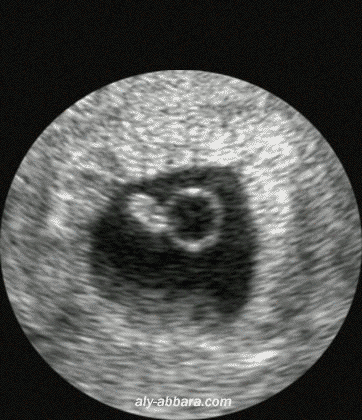

L'embryon n'est visible qu'à partir de cinq semaines et demi Avant, on ne voit que le sac de la grossesse Lorsqu'elle est effectuée entre 7 et 8 semaines, l'embryon mesure 10 à 15 millimètres, on ne voit même pas les membres niC'est la 12ème semaine de grossesse la taille du fœtus de 14 SA est de 10 cm et son poids de 45 g Tous les organes sont en place et poursuivent leur développement fonctionnel Le visageA partir de cette semaine, les maux de grossesse se feront plus présentsEt ça commence dès l'aurore vous vous réveillez avec des malaises matinaux, des douleurs articulaires dans le bassin, un mal de ventre persistant, vos jambes sont lourdes et vous avez des crampesL'hypersalivation vous donne tout le temps envie de cracher et la constipation vous guette aussi

Le fœtus à 6 semaines de grossesse A ce stade, les membres poussent et les doigts devraient commencer à se former les jours qui suivent L'embryon mesure 10 à 14 mm et pèse environ 1,7 g La tête, toujours grosse, représente près de la moitié du volume de son corps Son visage se développe aussi la langue, les narines et la 6 semaines de grossesse ventre À la sixième semaine de votre grossesse, il est très probable que votre corps soit toujours le même à l'extérieur Bien que votre bébé grandisse rapidement et que votre corps fasse de nombreux ajustements pour accueillir son nouveau locataire, le bébé est encore assez petit pour que vous ne voyiez pasLa première échographie de grossesse a lieu entre 11 SA et 13 SA 6 jours Elle n'est pas obligatoire mais fait partie des 3 échographies systématiquement proposées à la future maman et fortement recommandées (recommandations de la

A 5 semaines de grossesse, notre maman a fait une échographie précoce L'embryon était là mais elle n'a entendu aucun battement de coeur, et elle se demande si c'est normal La réponse deEst ce qu'on voit bien pour la 1ère échographie ?Cette première échographie peut être réalisée dès la 6 ème semaine de grossesse À ce stade de la grossesse, on peut déjà apprécier la présence de l'embryon et surtout l'existence d'un battement cardiaque, celui du futur bébé

Premières semaines de grossesse Sans aucun doute, le premier indice qui vous permettra de découvrir que vous êtes enceinte est l'absence de règles L'activité cardiaque du fœtus est visible aux alentours de 6 a 7 semaines de grossesse Parfois, à un jour près, elle peut encore être absente, d'où l 'importance de savoir attendre et de ne Echographie de datation comment ça se passe ?